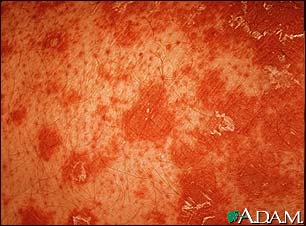

Pityriasis rubra pilaris - close-up

Pityriasis rubra pilaris is an uncommon skin condition. It is characterized by salmon-colored patches with scaling, clear areas of normal skin, and thick palms and soles. Hair follicles with keratin plugging is a characteristic sign. Typically the follicle is surrounded with a characteristic orange-red color.